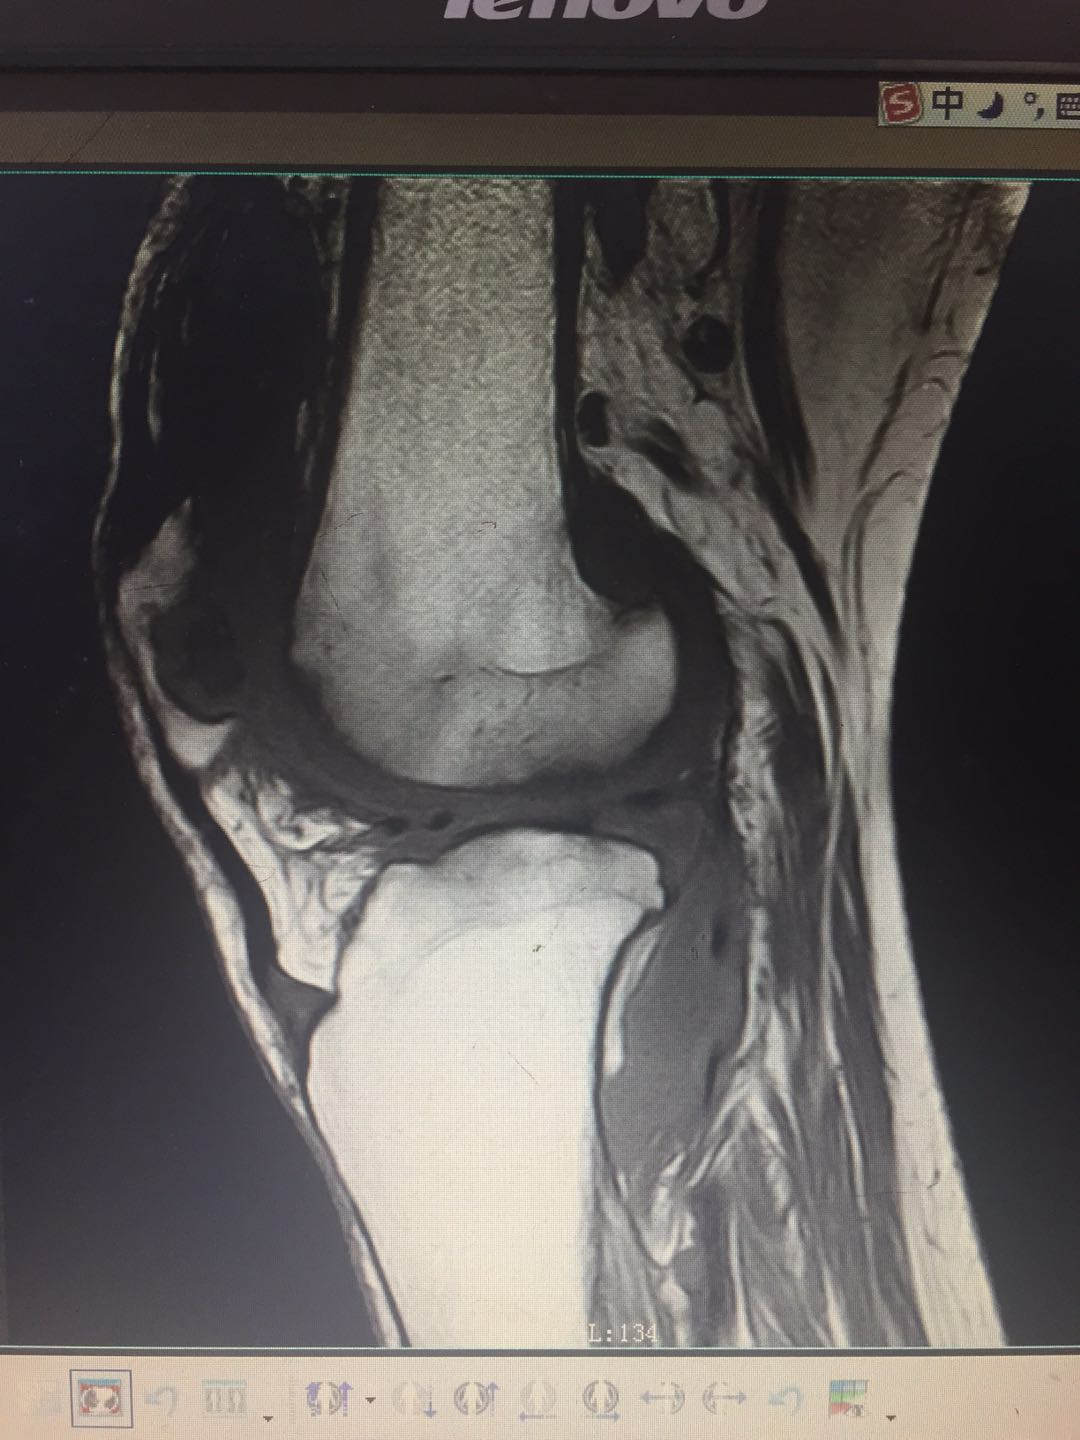

患   者:曾某某 ,女,69岁。

主   诉:左膝疼痛、肿胀、活动受限2年,加重3月,入院治疗。

既往史:2018年6月诊断为“左膝滑膜炎并关节积液”,予关节腔穿刺、理疗、药物治疗后病情好转。无明显潮热、盗汗。

专科检查:左膝部皮温稍增高,皮肤无发红,中度肿胀,呈屈曲位,内侧膝关节间隙处压痛明显,屈伸活动受限,被动活动时疼痛加重,左膝浮髌试验阳性,侧方挤压试验阳性,研磨试验阳性,抽屉试验阴性,肢端觉血运尚可,左下肢肌力感觉未见明显异常。

辅助检查:血沉:37mm/h,C反应蛋白:75.8ng/L,结核杆菌:阴性,降钙素原正常。余检查未见明显异常。

影像资料:

诊        断:

左膝骨性关节炎(K-L分级 4级);

左膝关节滑膜炎并关节积液。

治疗方案:

入院后拟行左膝关节置换术,但因炎性指标高,予口服消炎镇痛药物后稍下降,但仍高于正常。

结合患者左膝MRI讨论后于腰麻下行关节镜下左膝关节探查+滑膜切除术,术中见软骨广泛剥脱,术后滑膜、软骨病检:符合结核改变。予系统抗结核治疗。

专家指导

针对此病例诊断及治疗方案,杨述华教授指导如下:

此病例考虑诊断为骨关节炎。

治疗方法首先可以做膝关节表面置换,因为患者C反应蛋白、血沉都高于正常值,应采用抗生素的骨水泥。患者年龄较大,单纯的滑膜切除达不到治疗目的,如果要缩短治疗疗程,要彻底切除滑膜。